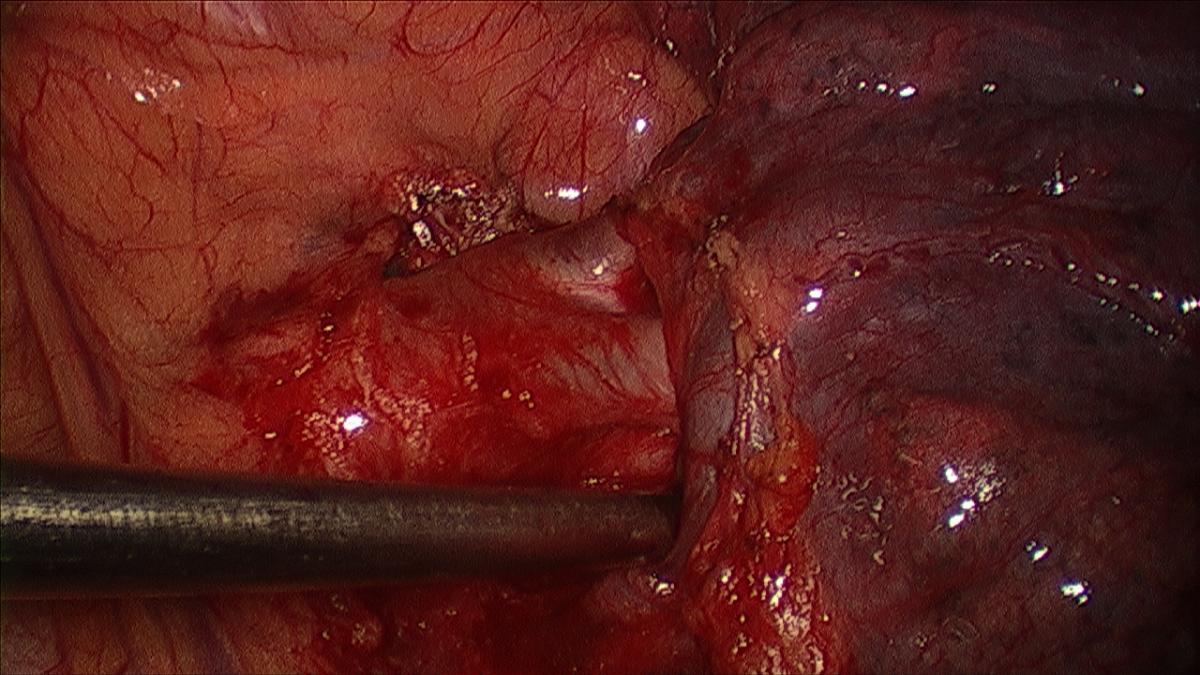

The camera is switched back to the anterior incision, the table rolled posteriorly, and the upper lobe retracted posteriorly. The superior pulmonary vein is dissected sharply and bluntly (sucker or peanut) circumferentially and distally until the trunk of the apical tri-segments and the lingular veins are clearly identified (Figure 3). Circumferential Isolation of the tri-segmental vein is done using a thoracoscopic right angle through the working incision, or by passage of a thoracoscopic curved vascular clamp via the posterior incision (Videos 1, 2).

Figure 3: Dissected apical pulmonary arterial branches.